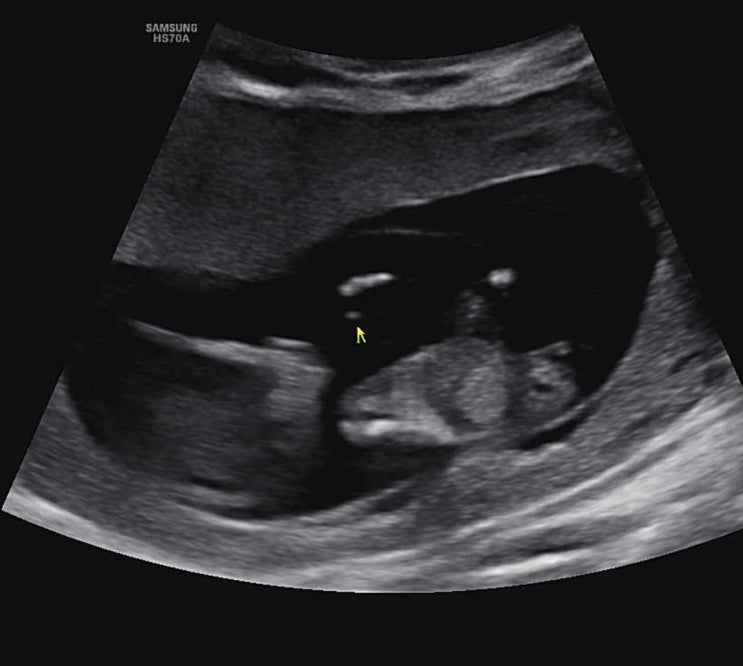

9주차 젤리곰 딸 심장소리, 12주차 초음파 각도법, 14주차 성별확인

9주차 이 시기에는 젤리곰 모양을 볼 수 있다고 한다. 이 모양이 젤리곰이라는데 내 눈엔 걍 쪼꼬미 사람ㅎ...